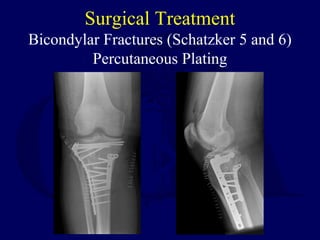

Surgical Treatment

Bicondylar Fractures (Schatzker 5 and 6)

Percutaneous Plating